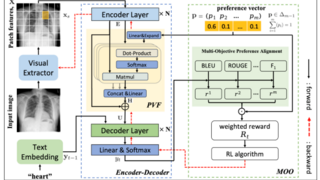

△论文图形摘要。该研究将有助于对大脑发育的深入研究,提供脑肿瘤、大脑发育相关疾病的治疗新路径。